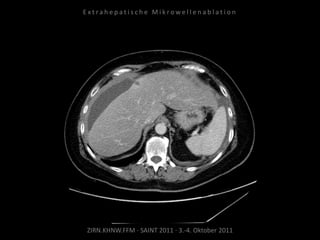

Ausgangsbildgebung:

CT vom 21.12.2009

Bildgebung vor MWA:

CT vom 14.07.2010

Metastase lateral der linken Niere

nahe Colon descendens progredient.